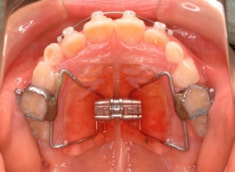

治療開始から6ヶ月後

治療開始から約1年1ヶ月後

治療開始から6ヶ月で反対咬合の解消は達成されておりますが、これで治ったわけではなく、上顎の劣成長を改善しなければならないので、ここからしっかりとフェイスマスクを使用していただきます。